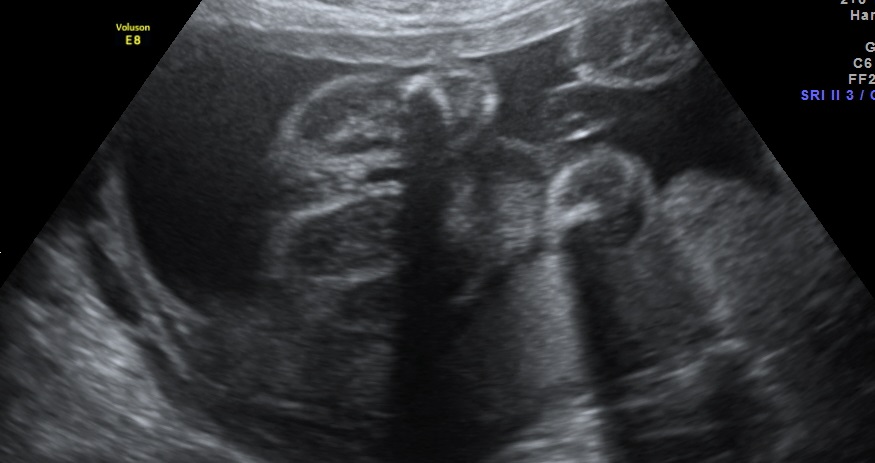

Can anybody see the gender? The legs are close together so it's hard to see. The person who performed the ultrasound thought boy but I'm not sure!

Thank you in advance :)

If the sonographer was a professional and they thought boy, I'd be inclined to believe them x

Thank you for your answer. That's what I thought too, the first time. I've had 3 ultrasounds. The first one said boy, the second said girl and this one said boy, that's why I don't really trust them :)

Boy lean